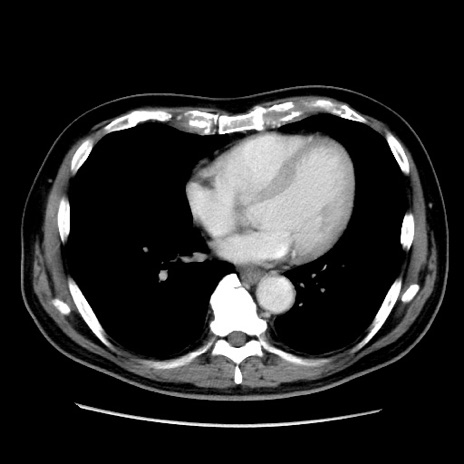

症例16(横断像)

【症例】 70歳代男性

【主訴】 腹痛、嘔吐

【現病歴】 約1ヶ月前より間欠的に腹痛と嘔吐あり、当院消化器内科を受診したところCTで多発する肝臓のLDAを指摘され、精査中であった。以降は消化器症状は安定していたが、2日前より嘔気と腹痛があり、同日より排便・排ガスが消失した。改善認めず、 本日、救急外来を受診した。

【既往歴】 大腸ポリープ切除後。

【身体所見】意識清明・会話良好、BT 36.3℃、BP 127/80mmHg、 P 80bpm、腹部:膨満あり、平坦・軟、上腹部正中および下腹部正中に圧痛あり、反跳痛なし、筋性防御なし。

【データ】WBC 7200、CRP 0.77